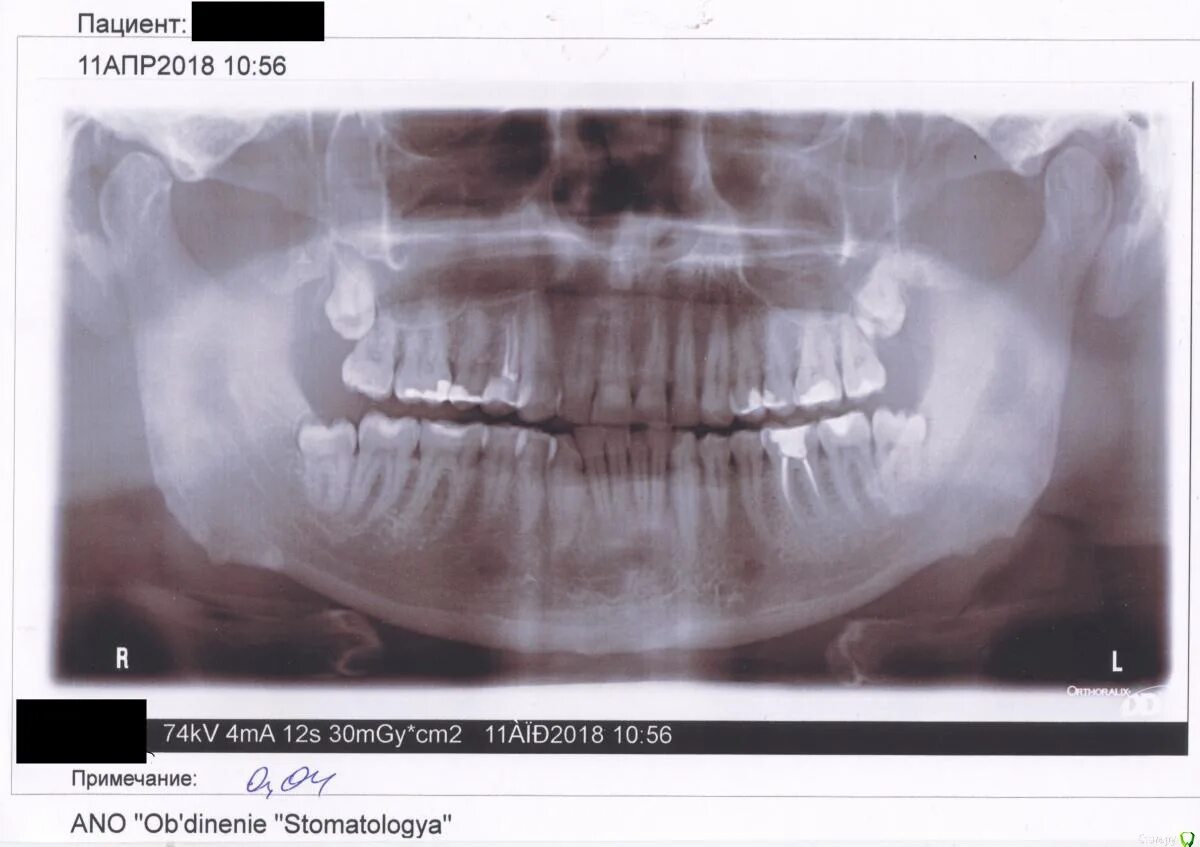

Зубы слева